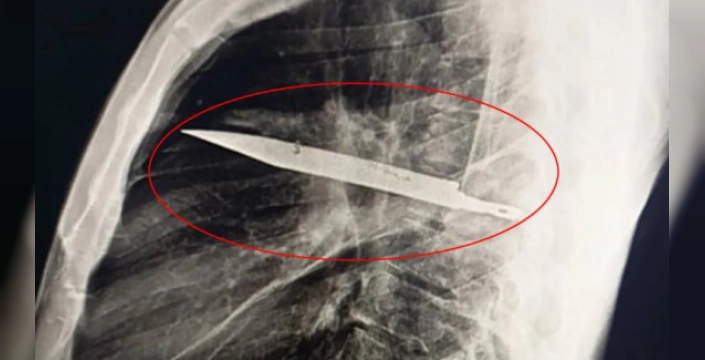

Tanzanya'da 44 yaşındaki bir adam, göğüs ağrısı ve sağ memesinden gelen beyaz irin şikayetiyle Muhimbili Ulusal Hastanesi'ne başvurdu. Yapılan röntgen incelemesinde, adamın göğsünde sekiz yıldır büyük bir bıçak parçası olduğu tespit edildi.

Hasta, sekiz yıl önce çıkan bir kavgada yüzünden, sırtından ve göğsünden yaralandığını, ancak o dönemde tedavi gördüğü hastanede görüntüleme imkanı olmadığı için vücudundaki yabancı cismin fark edilmediğini anlattı. Şaşırtıcı bir şekilde, bıçak tüm bu süre boyunca herhangi bir ağrı veya rahatsızlığa neden olmamıştı. Doktorlar, bıçağın sağ kürek kemiğinden girip hayati organlara zarar vermeden göğüste kaldığını ve irinin, bıçak çevresinde biriken ölü dokudan kaynaklandığını belirtti.